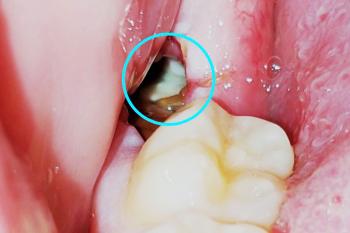

Tooth Fillings and Restorations

Root Canal Treatment

Tooth Extraction